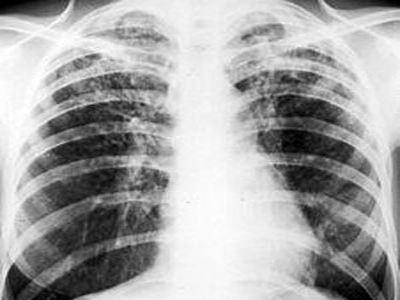

呼吸是人最基本和重要的事情,而“空调肺”会让肺纤维化,肺部越来越硬,导致氧气交换越来越少,逐步的缺氧状态让呼吸变得困难。